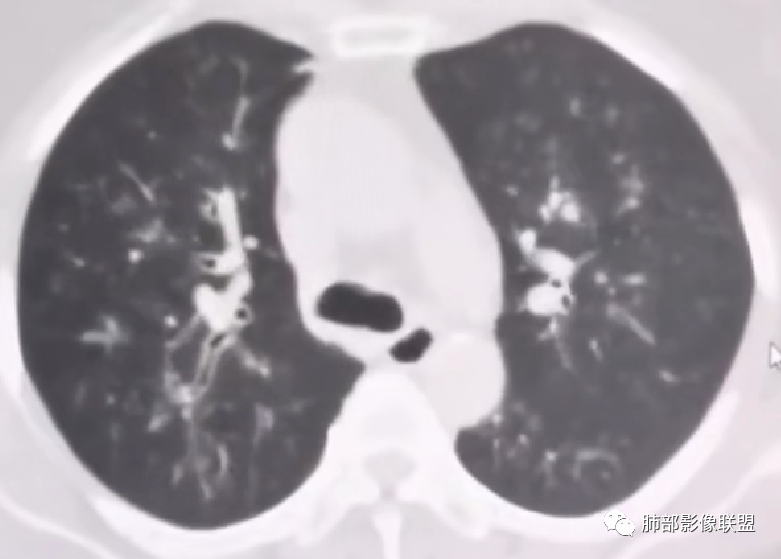

四.变应性支气管肺曲霉病(ABPA)

1.三四级以上支气管显著扩张,柱状扩张为主,常伴痰液嵌塞,远端支气管相对正常,强烈提示ABPA诊断!ABPA的支扩有时来得快去得快。

影像上表现为V形、Y形、葡萄状或指套状阴影,边缘清楚。

2.管腔扩张及管壁增厚(炎性反映),轨道征或环形影常比较显著;

3.病变远端的肺组织可有肺不张表现,或因侧支通气而出现过度充气征象。

另可有渗出性肺泡炎改变:肺实质内单发或多发斑片状密度增高影,上叶多见,可为一过性、游走性或持续较长时间。